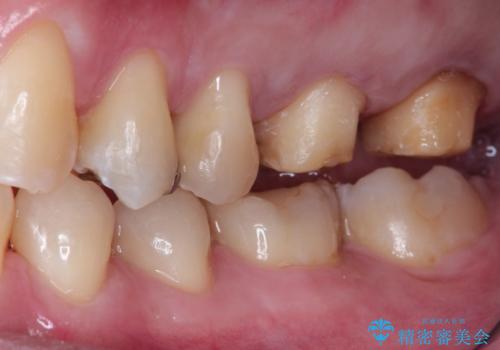

目立つ金歯を自然な色のオールセラミックへ

左上の奥歯に大きな金歯と、その後ろの歯が矯正治療用の仮歯が装着されていました。

これらの歯にオールセラミッククラウンを装着することとなりました。